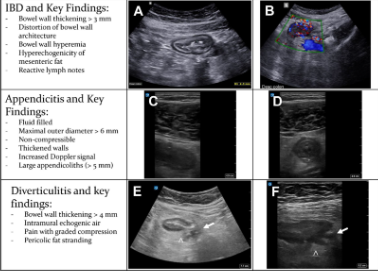

Gambar 1. Hasil temuan abnormal dari Intestinal Ultrasound